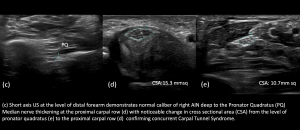

4.Anterior Interosseous Nerve with concurrent Carpal Tunnel Syndrome